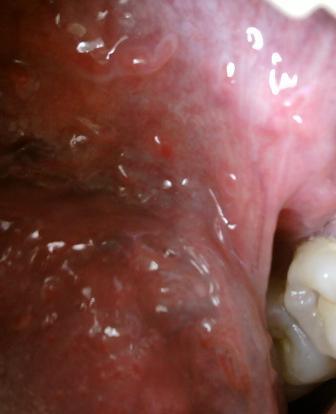

石家庄九州皮肤病医院 > 尖锐湿疣 > > > 尖锐湿疣比较青睐于哪些人群尖锐湿疣是一种传染性很强的疾病,一般性伴侣比较多,性生活比较复杂的人,患病的几率是比较高的,专家温馨提示:对于疾病的诊治应该引起重视,相信医学,经过正规的诊治,才能够更加迅速的得以治愈。

尖锐湿疣比较青睐于哪些人群尖锐湿疣不及时进行治疗,对于人体健康带来的伤害是很大的,治疗该病的关键就在于把握病情时机,最好是在病情尚不严重的情况下,就进行诊断治疗。毕竟初期是诊治的良机。